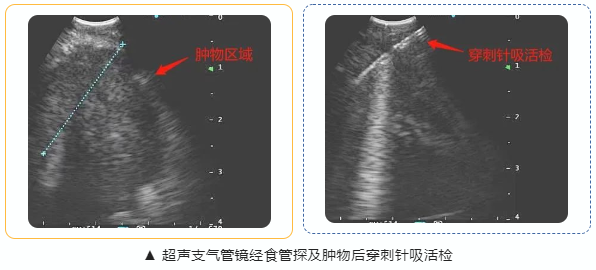

随后,我院呼吸与危重症医学科(二科)杜焰家副主任医师团队顺利为患者实施“超声支气管镜引导下经食管穿刺针吸活检术”(EBUS-TENA),成功取得标本,该术式穿刺更加精准,并发症发生率更低,术后病理诊断为“肺腺癌”,医生为患者进行了针对性的治疗。

相比传统的经支气管取检,经食管穿刺针吸活检术将超声支气管镜直接通过食管进镜,能够获取到很多支气管路径无法到达的标本,拓宽了技术的应用范围,大幅减少了诊断盲区,安全性高,能明显提高对肺部及纵隔肿瘤的诊断准确率,成为目前国内先进的呼吸介入诊断技术之一。